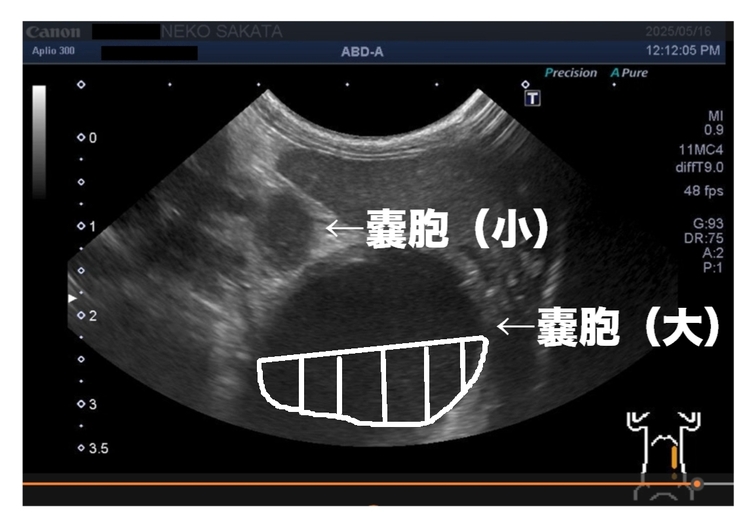

超音波で腎臓・膀胱をみてもらったところ

膀胱は非常にキレイな状態でしたが

2つある腎臓のうちの機能していない腎臓(水腎症)に白いモヤが溜まっていました。

これは腎臓で出血して血の鉄分がエコーで白く映っているか、

ばい菌が繁殖して膿んで白く映っているかのどちらかの可能性が高いそうです。